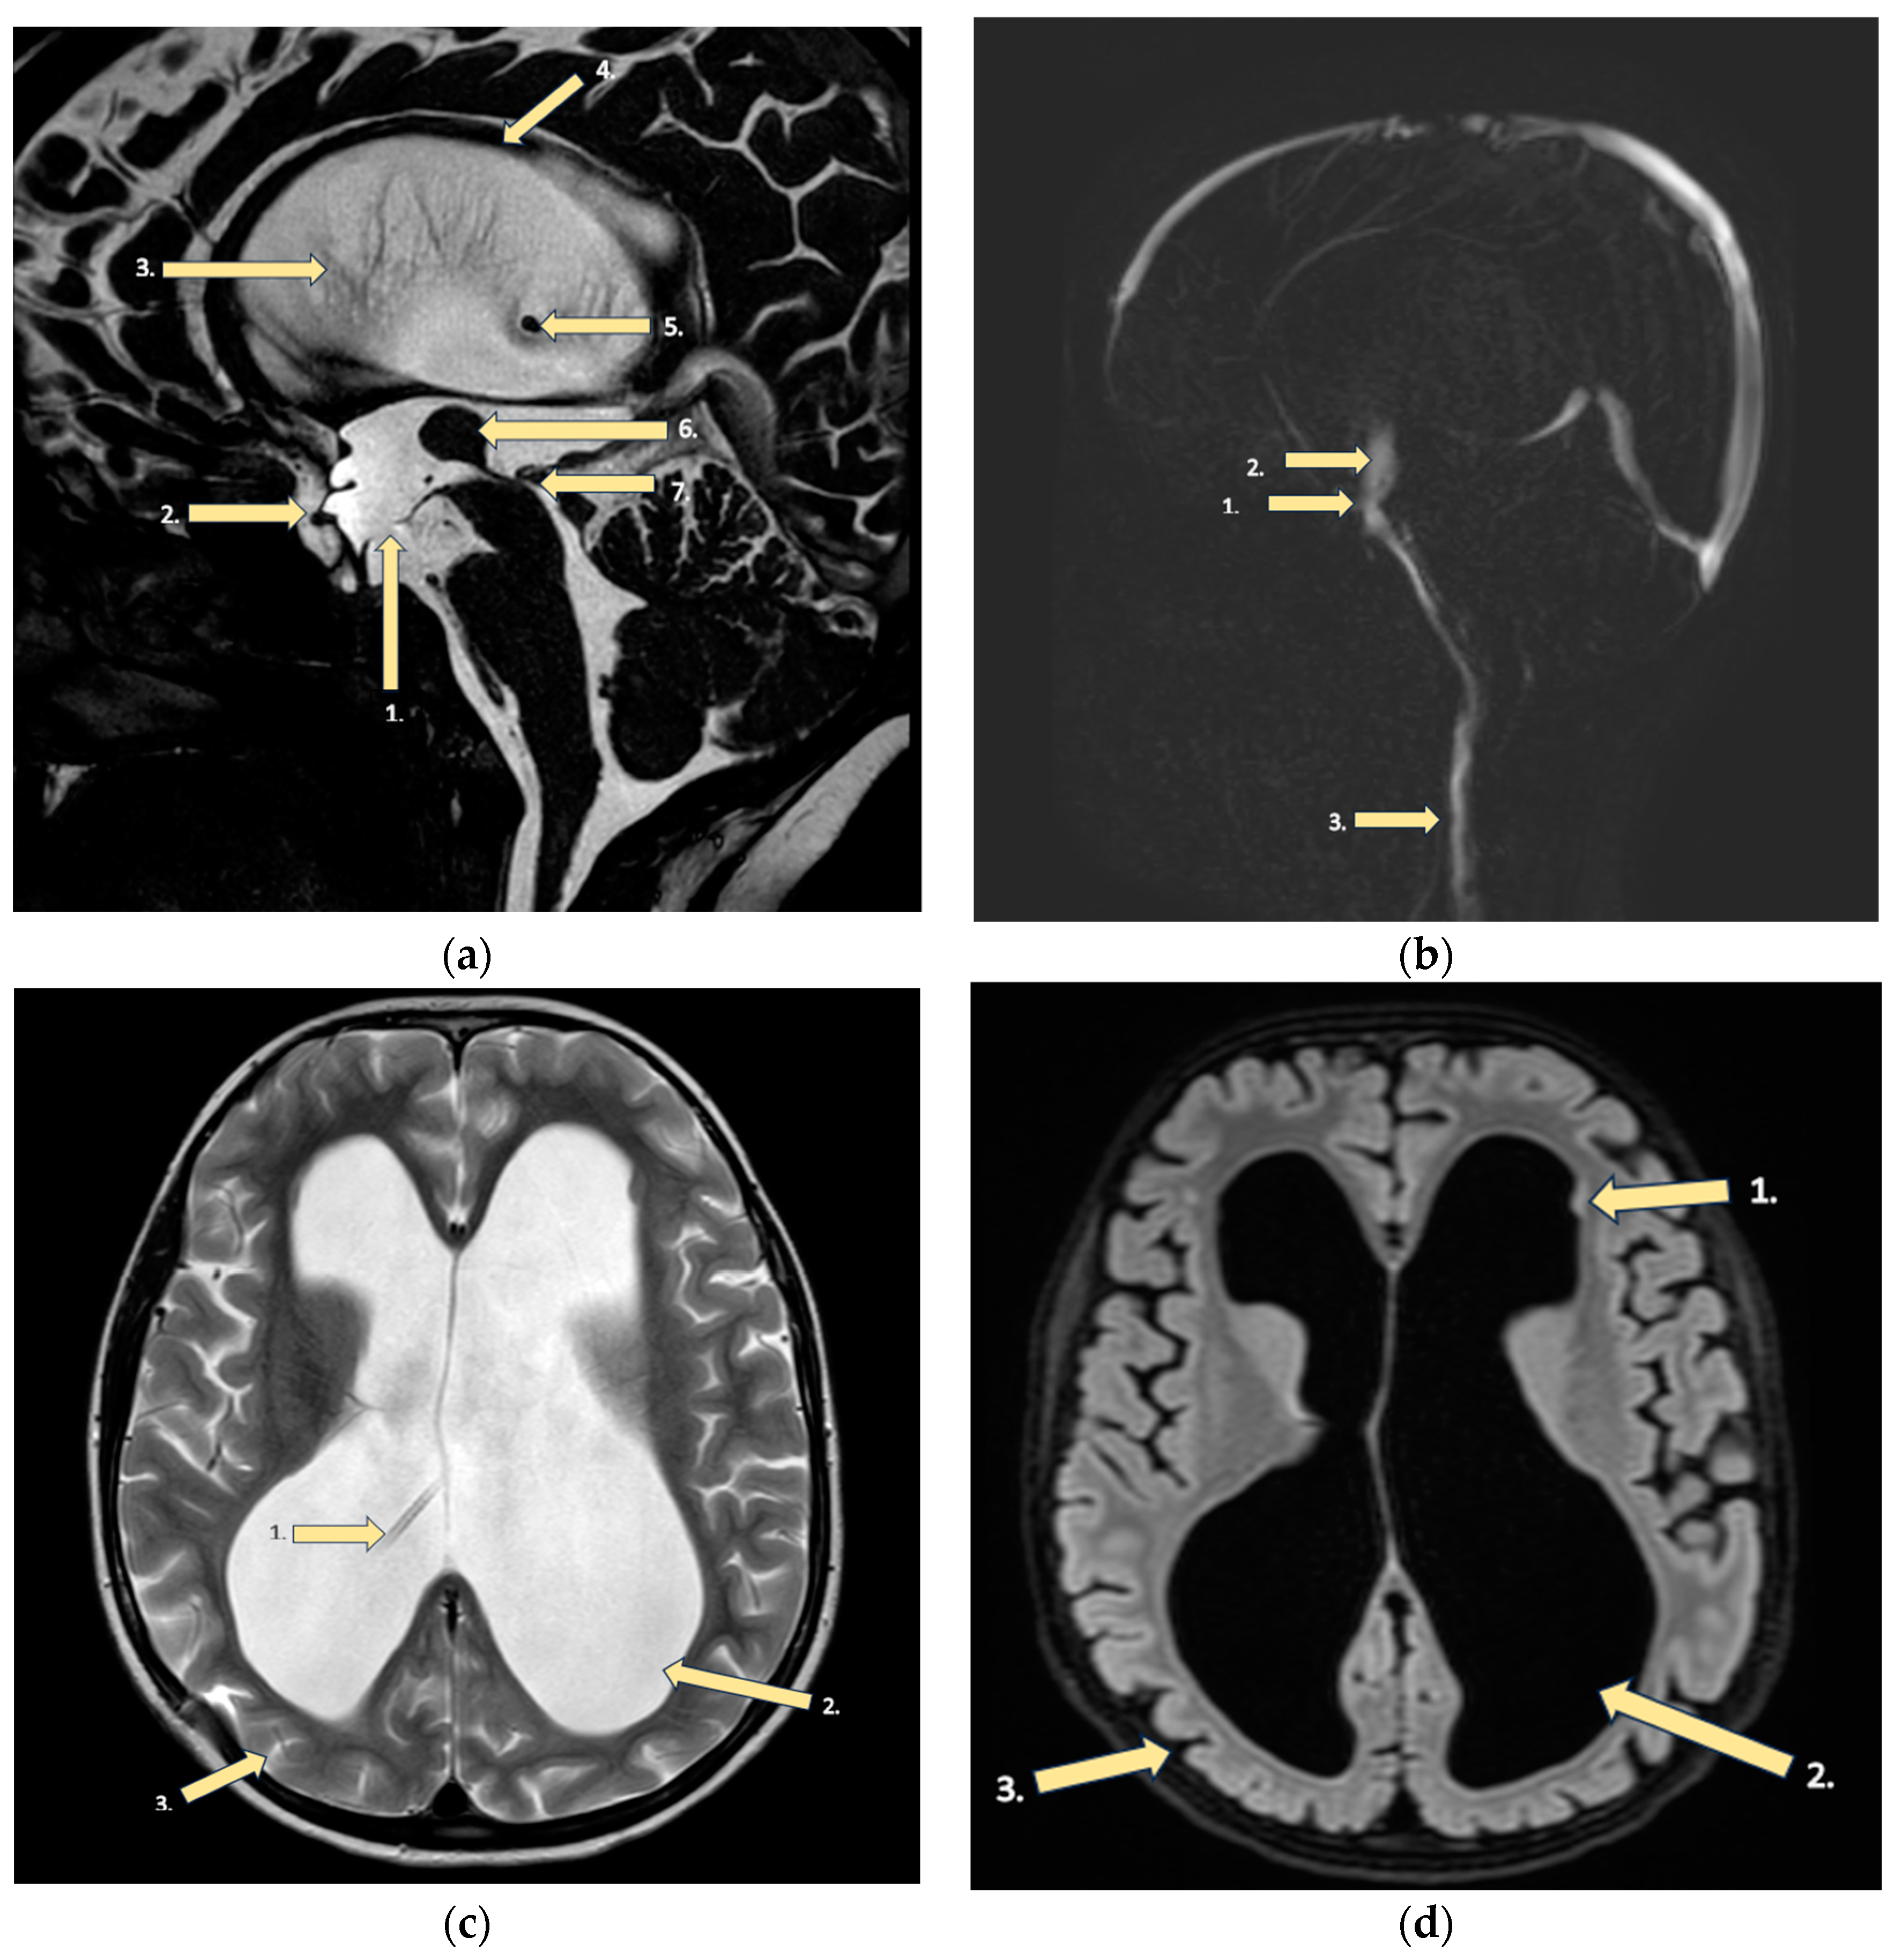

- Huhndorf, M.; Peters, S.; Cordt, J.; Margraf, N.G.; Salehi Ravesh, M.; Jansen, O.; Synowitz, M.; Cohrs, G. Venous 3D phase contrast magnetic resonance angiography increases diagnostic certainty in children with ventriculoperitoneal shunt and suspected shunt failure. Clin. Neuroradiol. 2023, 33, 1067–1074. [Google Scholar] [CrossRef] [PubMed]

- Plessen, K.J.; Wentzel-Larsen, T.; Hugdahl, K.; Feineigle, P.; Klein, J.; Staib, L.H.; Leckman, J.F.; Bansal, R.; Peterson, B.S. Altered interhemispheric connectivity in individuals with Tourette’s disorder. Am. J. Psychiatry 2004, 161, 2028–2037. [Google Scholar] [CrossRef]

- Goldstein, A.; Covington, B.P.; Mahabadi, N.; Mesfin, F.B. Neuroanatomy, Corpus Callosum. In StatPearls; StatPearls Publishing: Treasure Island, FL, USA, 2023. Available online: https://www.ncbi.nlm.nih.gov/books/NBK448209/ (accessed on 3 April 2023).

- Urbanik, A.; Guz, W.; Gołębiowski, M.; Szurowska, E.; Majos, A.; Sąsiadek, M.; Stajgis, M.; Ostrogórska, M. Assessment of the corpus callosum size in male individuals with high intelligence quotient (members of Mensa International). Beurteilung der Größe des Corpus callosum bei männlichen Probanden mit einem hohen Intelligenzquotienten (Mitglieder von Mensa International). Radiologie 2023, 63, 49–54. [Google Scholar]

- Andronikou, S.; Pillay, T.; Gabuza, L.; Mahomed, N.; Naidoo, J.; Hlabangana, L.T.; du Plessis, V.; Prabhu, S.P. Corpus callosum thickness in children: An MR pattern-recognition approach on the midsagittal image. Pediatr. Radiol. 2015, 45, 258–272. [Google Scholar] [CrossRef] [PubMed]